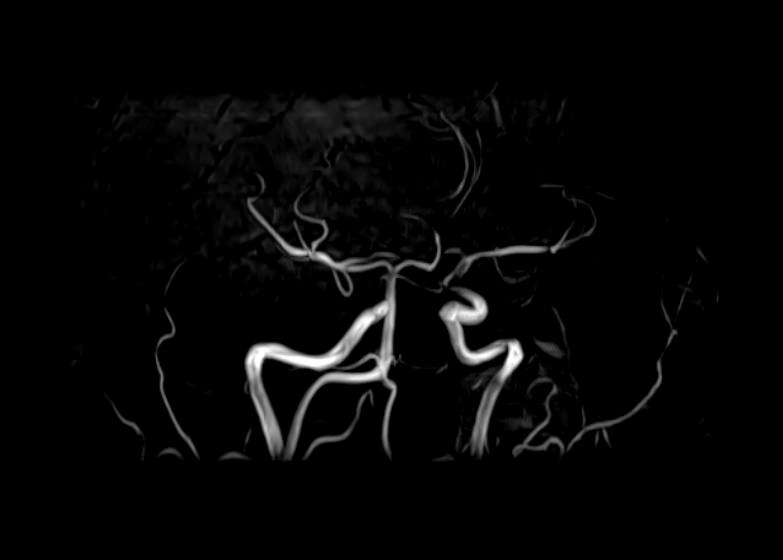

Кроме того, в области шеи проходят крупные кровеносные сосуды, кровоснабжающие все структуры головного мозга и мягких тканей головы. К ним относятся плечеголовной ствол, сонные и позвоночные артерии, которые далее в полости черепа соединяются между собой в Виллизиев круг. Это анатомическое образование позволяет компенсировать мозговой кровоток при патологических состояниях.

Часто различные нарушения в шейном отделе позвоночника приводят к ухудшению кровоснабжения головного мозга. Опухоли и дегенеративно-дистрофические заболевания шейного отдела позвоночника могут нарушать работу головного мозга. Атеросклеротические бляшки в сосудах шеи могут стать причиной преходящих нарушений мозгового кровообращения (транзиторных ишемических атак) и привести к развитию инсульта. Поэтому важно в комплексе детально визуализировать эти анатомические структуры вместе с оценкой состояния кровеносной системы головы и шеи.

• участки сужения, извитость, образование петель и перегибов сосудов;

• нарушения оттока крови за счет тромбообразования в венозном русле;

• ангиомы, сосудистые мальформации;